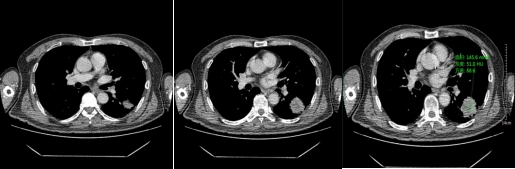

不同性质的结节,因为内部组织成份不同所以强化的方式不同,结节的供血方式也有不同,所以不同性质的肺结节,强化的方式也是不同。比如:急性期炎性肺结节因为组织成份多为肉芽组织,血管丰富,所以增强后明显强化,往往比平扫示强化程度高60HU以上;慢性期炎性肺结节,其主要成份示纤维组织,强化比较轻微,CT值较平扫多高20HU。

恶性实性结节,病变内含有肿瘤组织血管,强化程度不如急性炎性结节,增强CT扫描多升高20-60HU之间。

动脉期

静脉期

对于实性结节、亚实性磨玻璃结节具有以上恶性征象,就需要进一步CT增强扫描。增强CT的意义在于观察结节与周围血管的关系,结节本身有没有血供及血供的程度。因此,需要专业医师根据结节强化的方式、程度,结节本身的形态特征,与周围组织的关系,全面评估结节的性质,判断结节良恶性,为患者的治疗制定下一步措施。